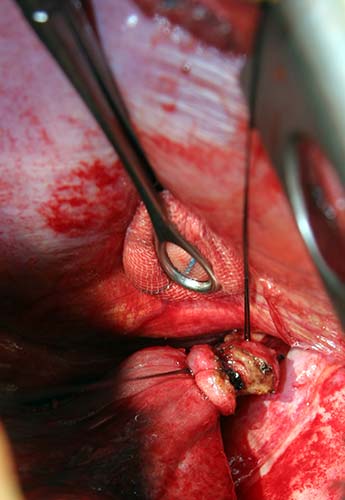

Flexible bronchoscopy revealed normal bronchial anatomy (Video 1). There was no evidence of stricture. All segmental airways were present. A right thoracotomy was performed. The sequestration appeared as a bluish mass incorporated in the substance of the right lower lobe (Figure 6). The artery supplying the sequestration was visualized coursing through the inferior pulmonary ligament and divided (Figures 7, 8; Video 2). Alternating single and double lung ventilation, the sequestration was identified along the basolateral margin of the right lung (Video 3) with a clear line of demarcation. A combination of electrocautery and 4.8mm endoscopic staplers (Video 4) was used to separate normal lung from the sequestration (Video 5). Fibrin glue was applied to all staple lines. Normal bronchial airways were not divided and the remaining lower lobe inflated normally (Video 6). The post-surgical course was uncomplicated and the patient was discharged on post-operative day four. Pathology revealed parenchymal cyst formation with chronic inflammation and organizing pneumonia.

| Figure 6: Intraoperative image of bluish-hued sequestration | Figure 7: Feeding artery ligated and partially divided | Figure 8: Cut end of feeder artery off aorta |